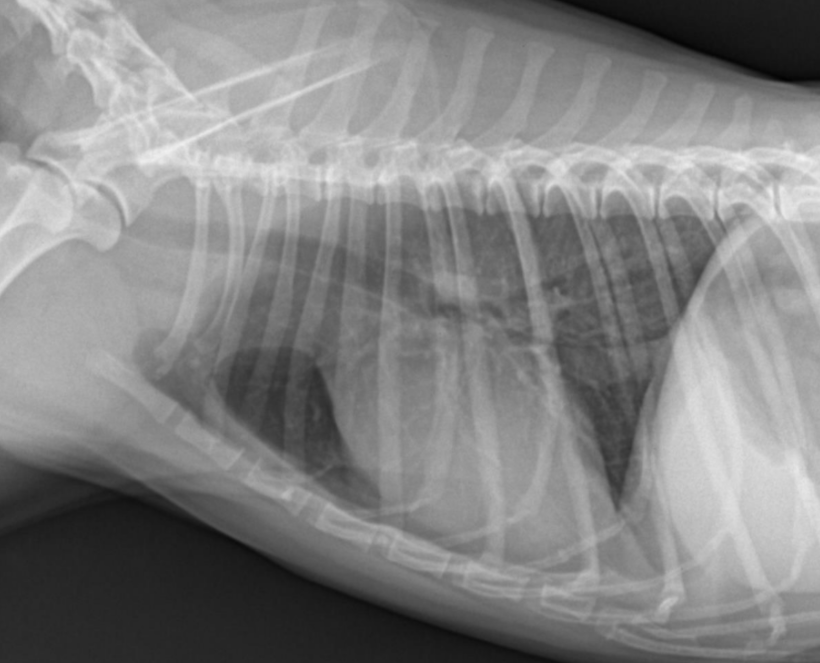

Intestinal perforation (์ฅ์ฒ๊ณต)

- ๋ฐ์ด, ๊ตฌํ , ๊ธฐ๋ ฅ์ ํ, depression ๋ฑ์ผ๋ก ๋ด์, 1์ฃผ ์ ๊ต์ history.

- ์ฅ์ฒ๊ณต โ ๋ด์ฉ๋ฌผ ๋น ์ ธ๋์ด โ ๋ณต๋ง์ผ์ผ๋ก ์งํํ ๊ฒ. (1์ฃผ์ผ์ด๋ฉด ๋ณต๋ง์ผ์ผ๋ก ์งํํ๊ธฐ ์ถฉ๋ถ!)

- ๋ฐฉ์ฌ์ ์ serosal detail ์ ํ (๋งค์ฐ ์ฌํ ์ผ์ฆ), ๋ณต๊ฐ ๋ด ์ ๋ฆฌ gas ๋ง์.

- ์ด๋ฌผ, ๊ต์, ์ฐฝ์์ ์ํด ์์๋ ์ ์์.